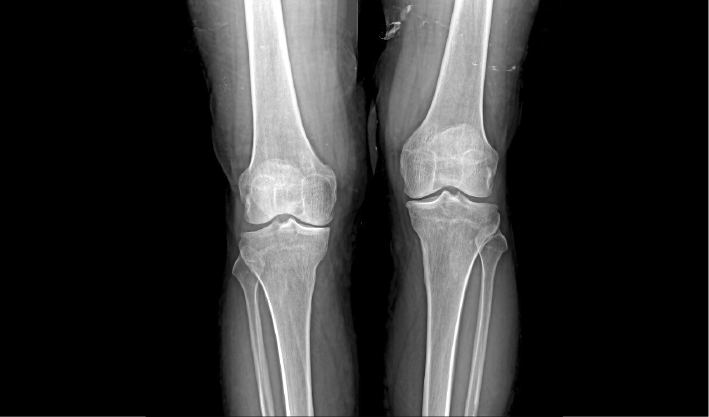

配合十軸智能全自動操控,實現六向跟蹤和一鍵自動擺位切換,融合高端配置,帶來一流的圖像,簡便操控,快捷流程,輔助醫生快速精準診斷。

消除線噪聲的同時不損失圖像細節,保持邊緣和分辨率,不會引入新偽影,增加圖像銳利度。

管球無位移,消除運動誤差,提高拼接成功率。

重疊區域面積小,減少曝光次數,減少輻射劑量。

AEC自動曝光和影像均衡算法,保證拼接圖像統一亮度和對比度。